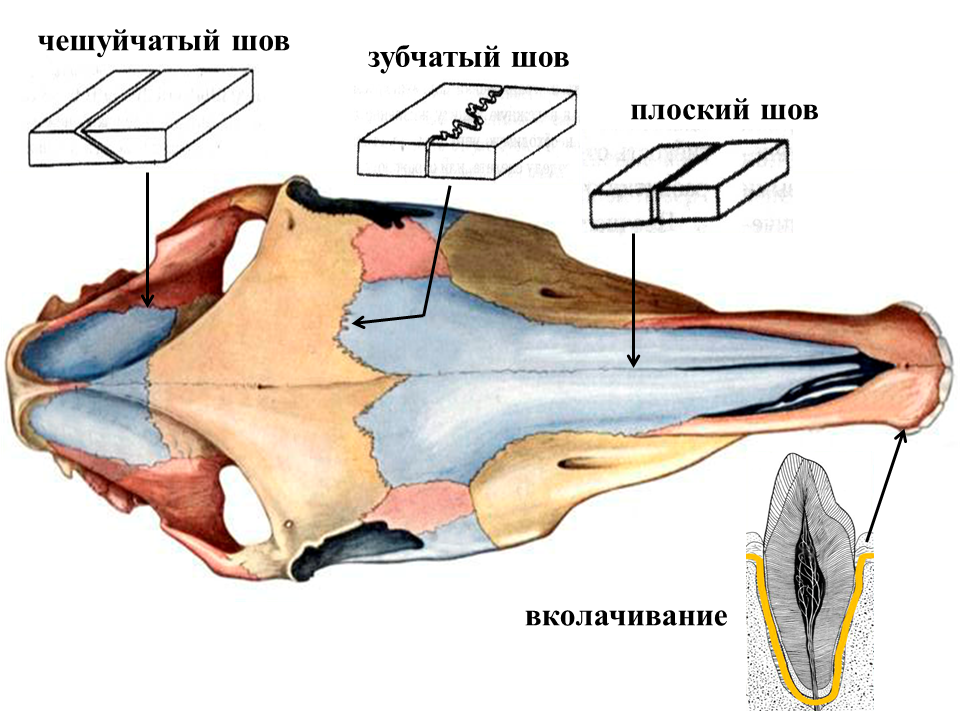

Структура и анатомия синдесмоза: научные иллюстрации